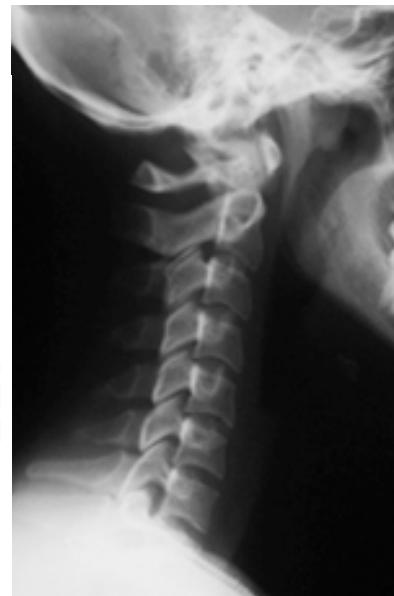

Cervical Spine Radiographs

Lateral View:

- All C-vertebrae & upper T1

- Prevertebral soft tissue width

- Four parallel curves:

- Front of vertebral bodies

- Back of vertebral bodies

- Posterior borders of lateral masses

- Bases of spinous processes

C2 Odontoid Fractures

- Diagnosis: Standard lateral and open-mouth odontoid radiographs; CT scan for difficult cases